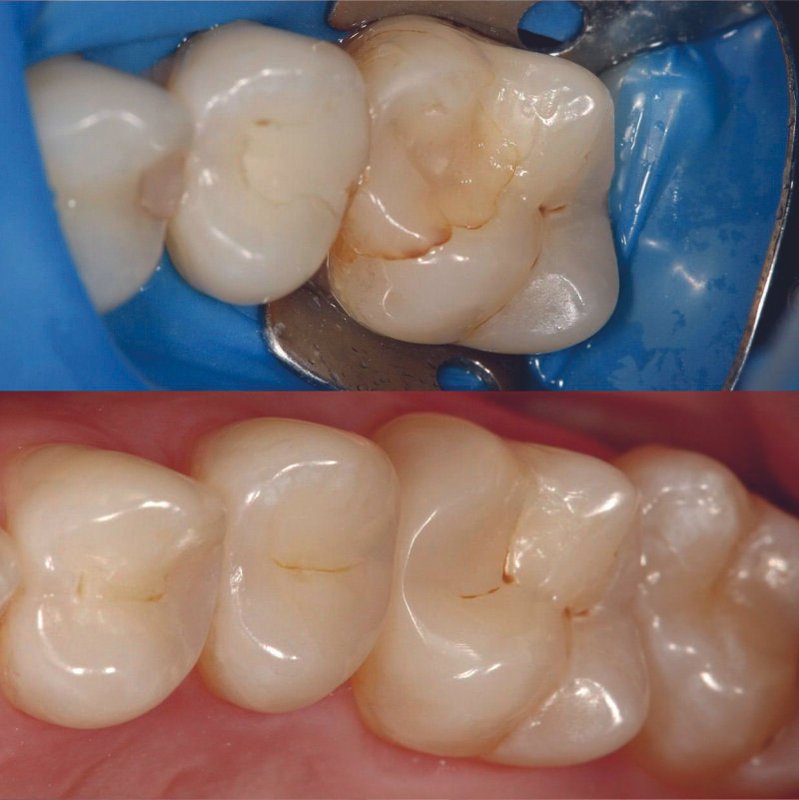

Фотогалерея